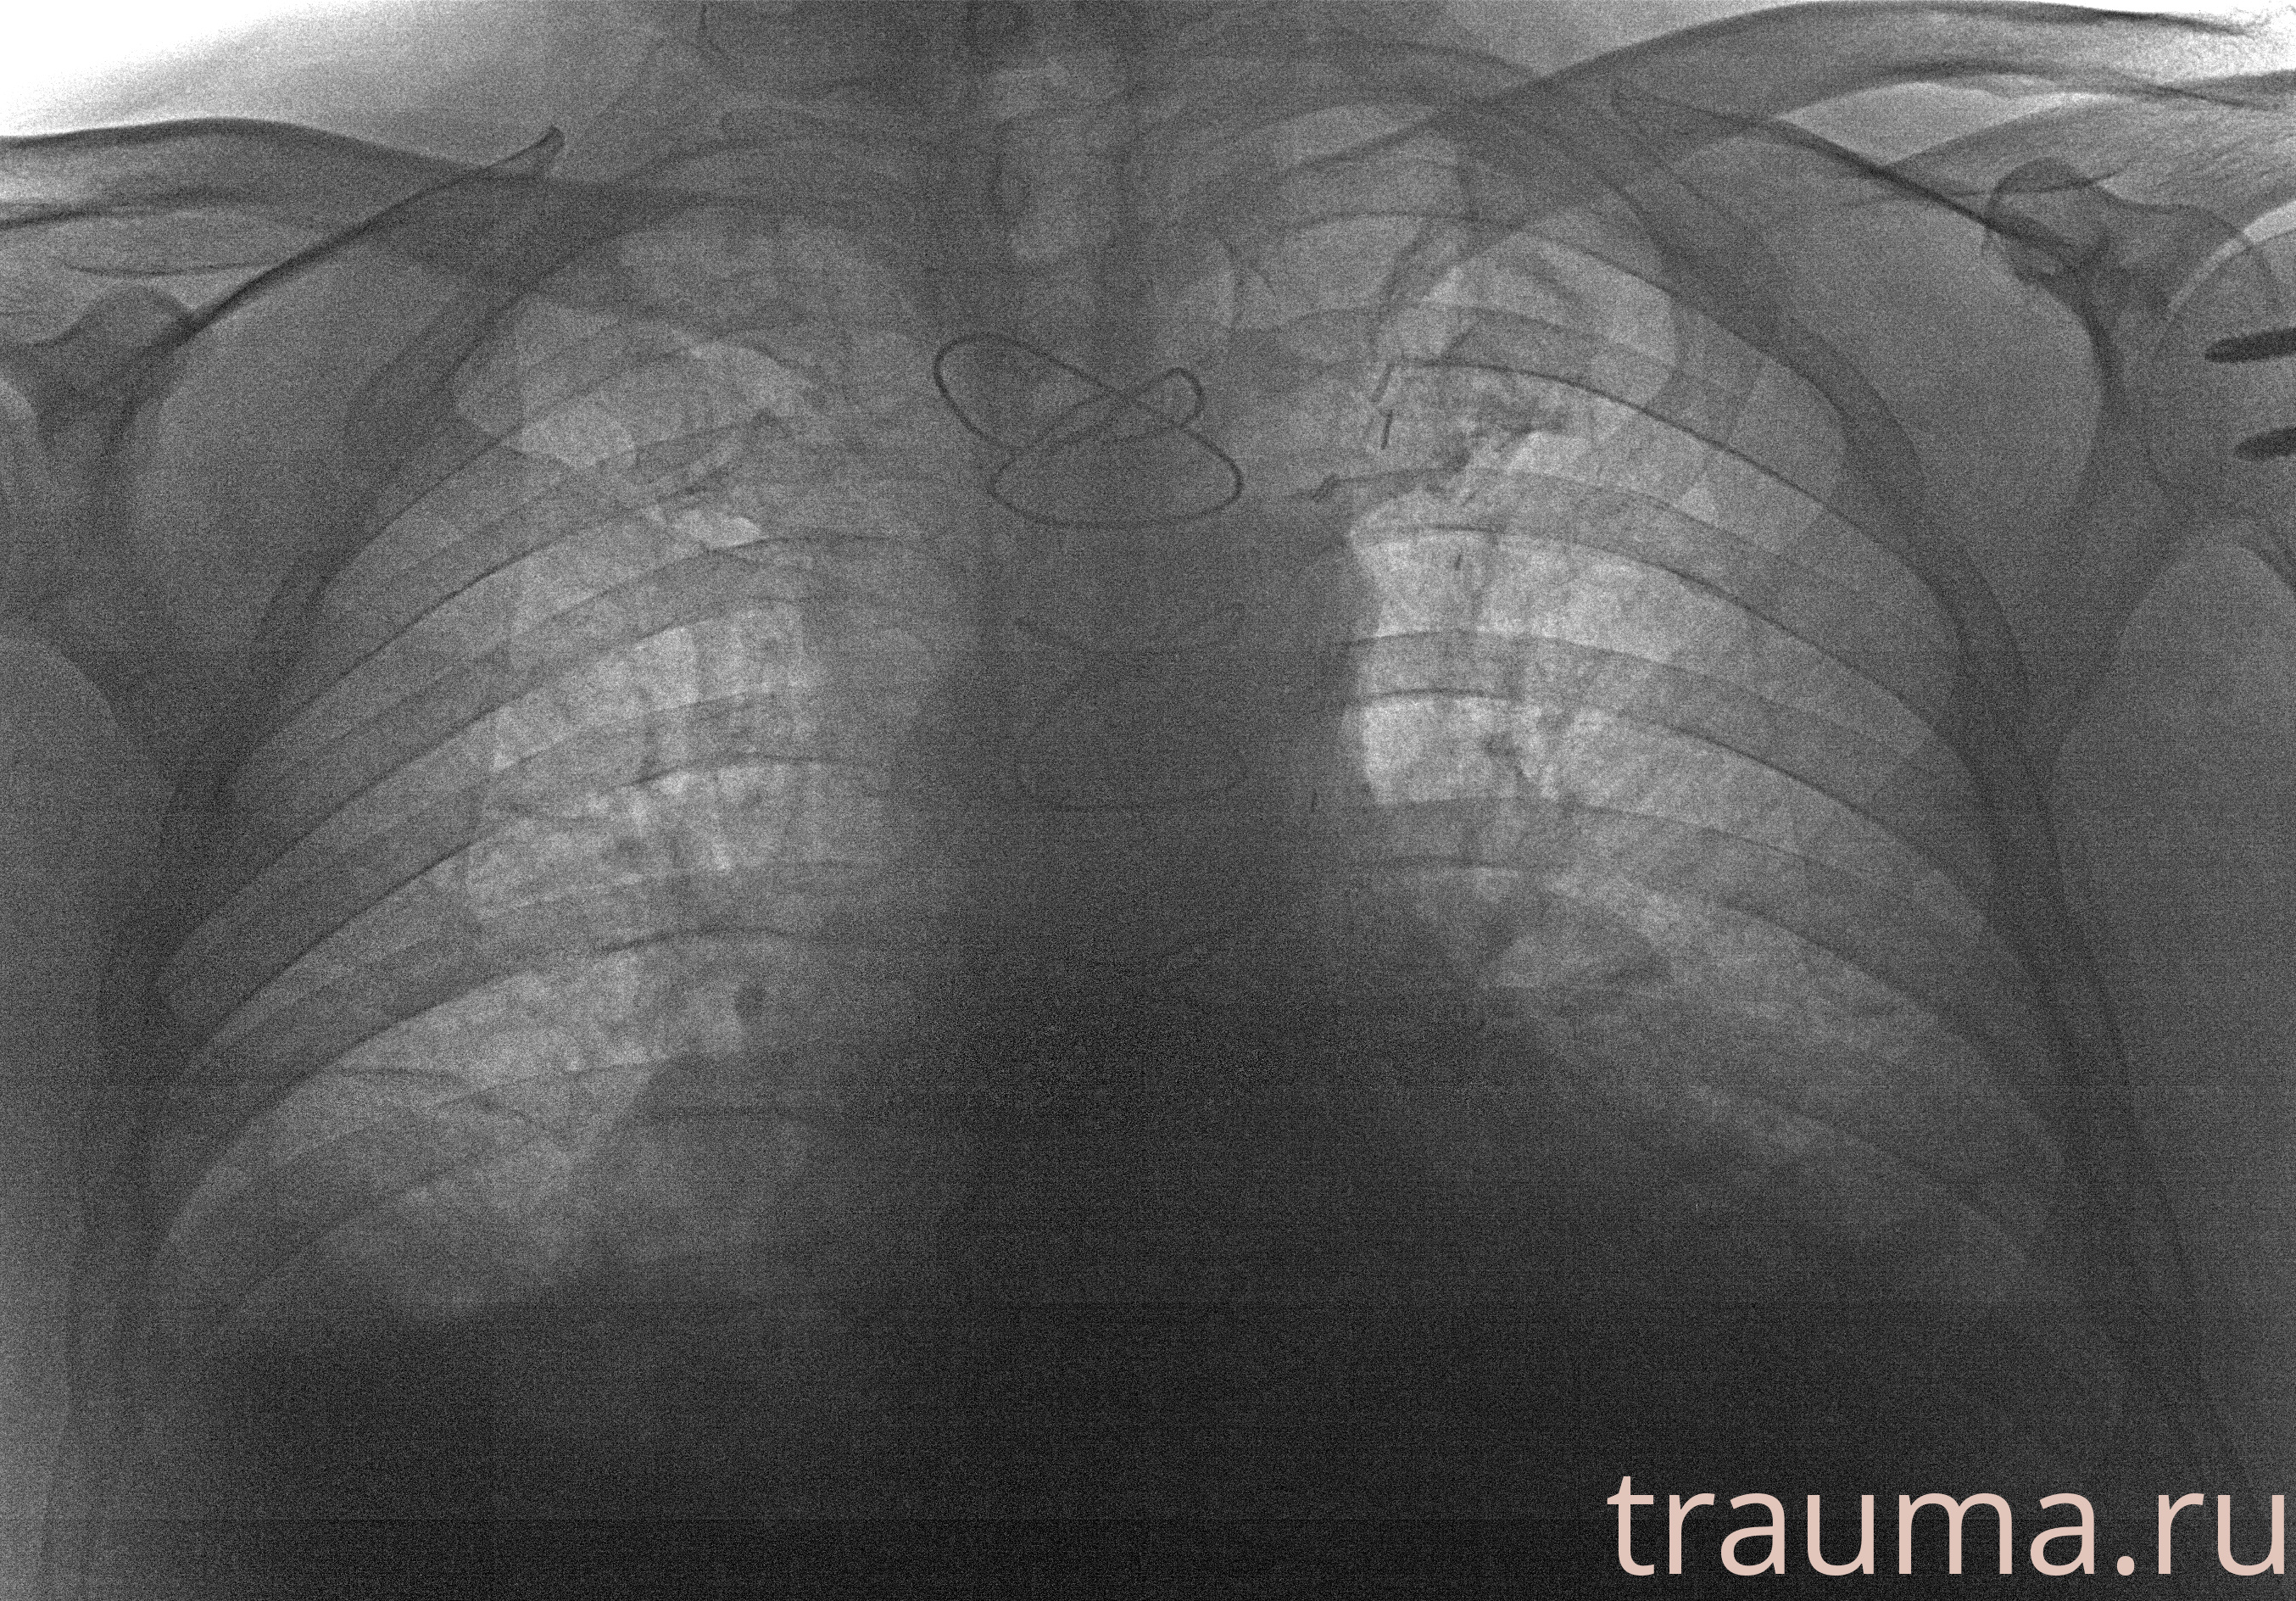

Рентгенограммы

Рентген на дому: по вашему адресу приезжает врач-рентгенолог, травматолог-ортопед с мобильным рентгеновским аппаратом, проводит диагностику травмы или заболевания, делает необходимые рентгенограммы, дает рекомендации по дальнейшему лечению. Получить качественные снимки в домашних условиях возможно благодаря уникальной методике, разработанной МосРентген Центром для института  Склифосовского